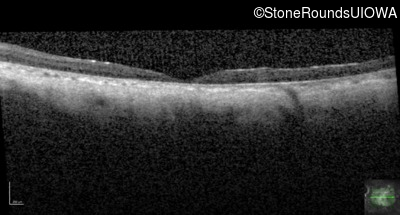

Optical Coherence Tomography - Left - 10/200 sc

Exemplar / OCT Stack